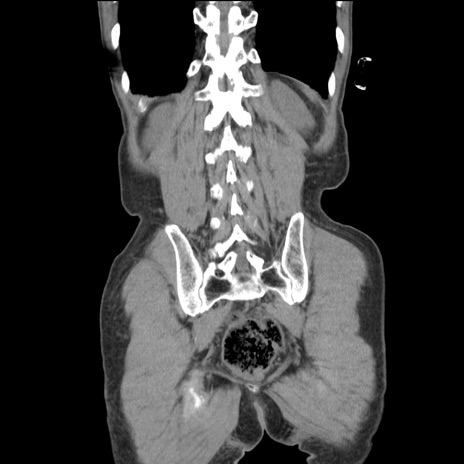

症例11(冠状断像)

【症例】 60歳代男性

【主訴】 下腹部痛

【現病歴】 本日夜中より下腹部痛の症状認め、受診。

【既往歴】 膀胱癌(膀胱全摘+尿管皮膚瘻術) 、胃癌術後

【身体所見】 BT 35.3℃、PR 58/min、BP 136/98mHg、腹部平坦、軟、腸蠕動音±、ストマ留置あり、左上腹部~正中部に圧痛あり、反跳痛なし。

【データ】WBC 5100、CRP0.01